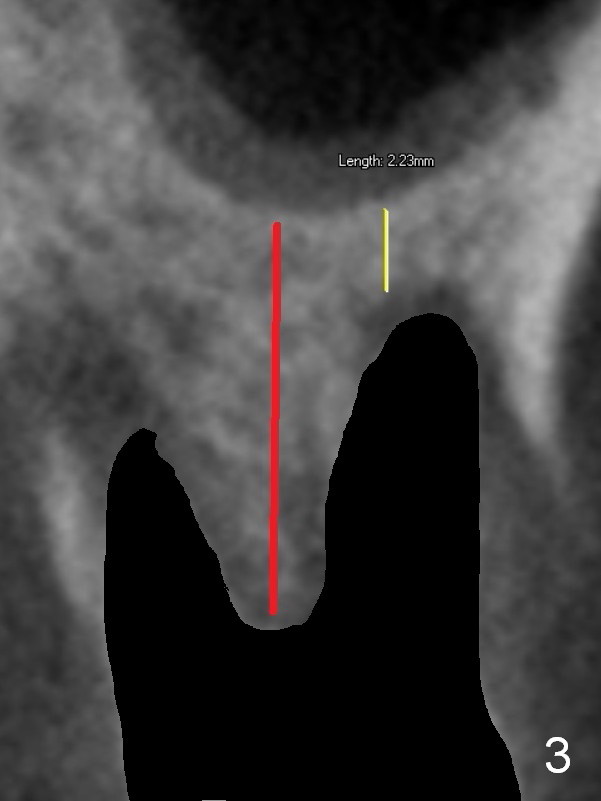

Preop CT shows that the septum appears to be able to hold a 11 mm long implant (Fig.1 sagittal section). There are periapical radiolucent lesions of the buccal (Fig.2 (coronal section) B) and palatal roots; bone height above the buccal apex is ~ 2 mm (Fig.3). When the tooth #14 is extracted, a 1.6 mm pilot drill is used to start osteotomy in the middle of the fairly thin septum (Fig.3 red line, Fig.4 S). It is hoped that Magic Expanders (ME) can enlarge the osteotomy by pushing the buccal and palatal bone plates of the septum outward (Fig.5 arrows).